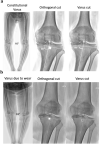

Methods: From a consecutive series of 918 primary TKAs, 266 (29%) knees received CT-based posterior-stabilized cemented custom TKA. In addition to a preoperative CT-scan, pre- and post-operative radiographs of weight-bearing long leg, anterior-posterior and lateral views of the knee were obtained, on which the FMA, TMA and HKA angles were measured. CT-based three-dimensional (3D) models enabled to correct for cases with bony wear by referring to the non-worn areas and to estimate the native pre-arthritic angles. The alignment technique aimed to preserve or restore constitutional alignment (CA) within predetermined limits, by defining a 'target zone' based on three criteria: 1) a ± 3° (range 87°-93°) primary tolerance for the femoral and tibial resections; 2) a ± 2° secondary tolerance for component obliquity, extending the bounds for FMA and TMA (range 85°-95°); 3) a planned HKA angle range of 175°-183°. Agreement between preoperative, planned and postoperative measurements of FMA, TMA and HKA angle were calculated using intra-class correlation coefficients (ICC).

Results: Preoperative radiograph and CT-scan measurements revealed that, respectively, 73 (28%) and 103 (40%) knees were in the 'target zone', whereas postoperative radiographs revealed that 217 (84%) TKAs were in the 'target zone'. Deviation from the planned angles were - 0.5° ± 1.8° for FMA, - 0.5° ± 1.8° for TMA, and - 1.1° ± 2.1° for HKA angle. Finally, the agreement between the planned and achieved targets, indicated by ICC, were good for FMA (0.701), fair for TMA (0.462) and fair for HKA angle (0.472).